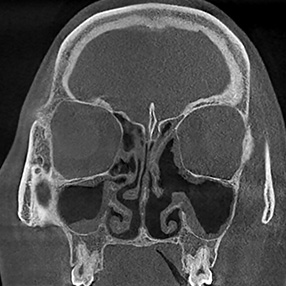

※ 축농증 수술 후 생길 수 있는 부작용으로는 출혈, 감염, 염증이 있을 수 있습니다.

본 사진은 의료기관에서 진료를 본 환자이고, 전후 사진 인물이 동일인이며,동일조건에서 촬영이 되었습니다.